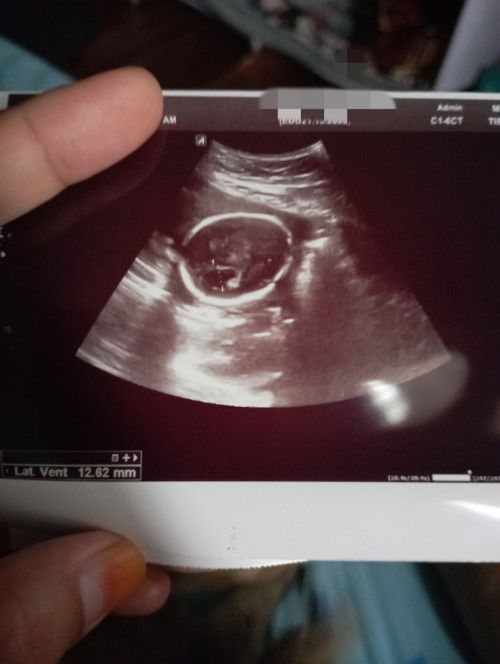

Cecair di kepala.

Ada sesiapa yg ada pengalaman, cecair berlebihan di kepala. Kalau ada, saya amat berterima kasih untuk menerima setiap cerita dan pandangan tersebut. #seriusnanya #firstmom #ingintahu #firstbaby #pleasehelp

ya, inshaallah. makin berkurang cecair tu. lepas saya scan tu, saya rujuk di KK. Doc KK bagi follow up dengan pakar asap. Semoga baby sis dalam keadaan baik baik saja. Doc saya pesan, selalu pujuk/borak dengan baby suruh kawal cecair, sebab nak kawal cecair tu baby saja. Alhamdulillah baby dengar kata.